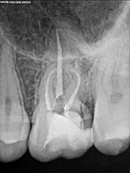

Root Canal Cases